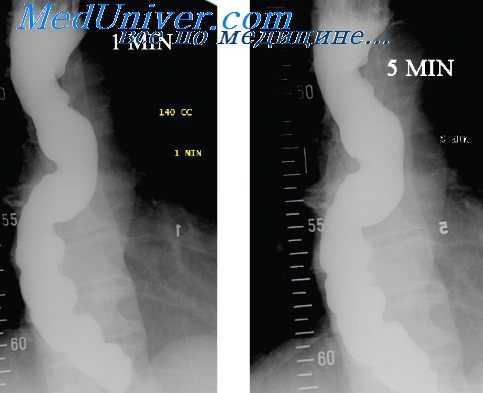

При рентгенографии с контрастированием просвет пищевода расширен, заполнен пищевыми массами. Контрастное вещество оседает длительно, в виде хлопьев снега. Эвакуация контраста из пищевода значительно замедлена (более нескольких часов). Эзофагеальная манометрия позволяет вывить нарушения моторики пищевода. Для дифференциальной диагностики проводится УЗИ и МСКТ органов брюшной полости, сцинтиграфия пищевода.